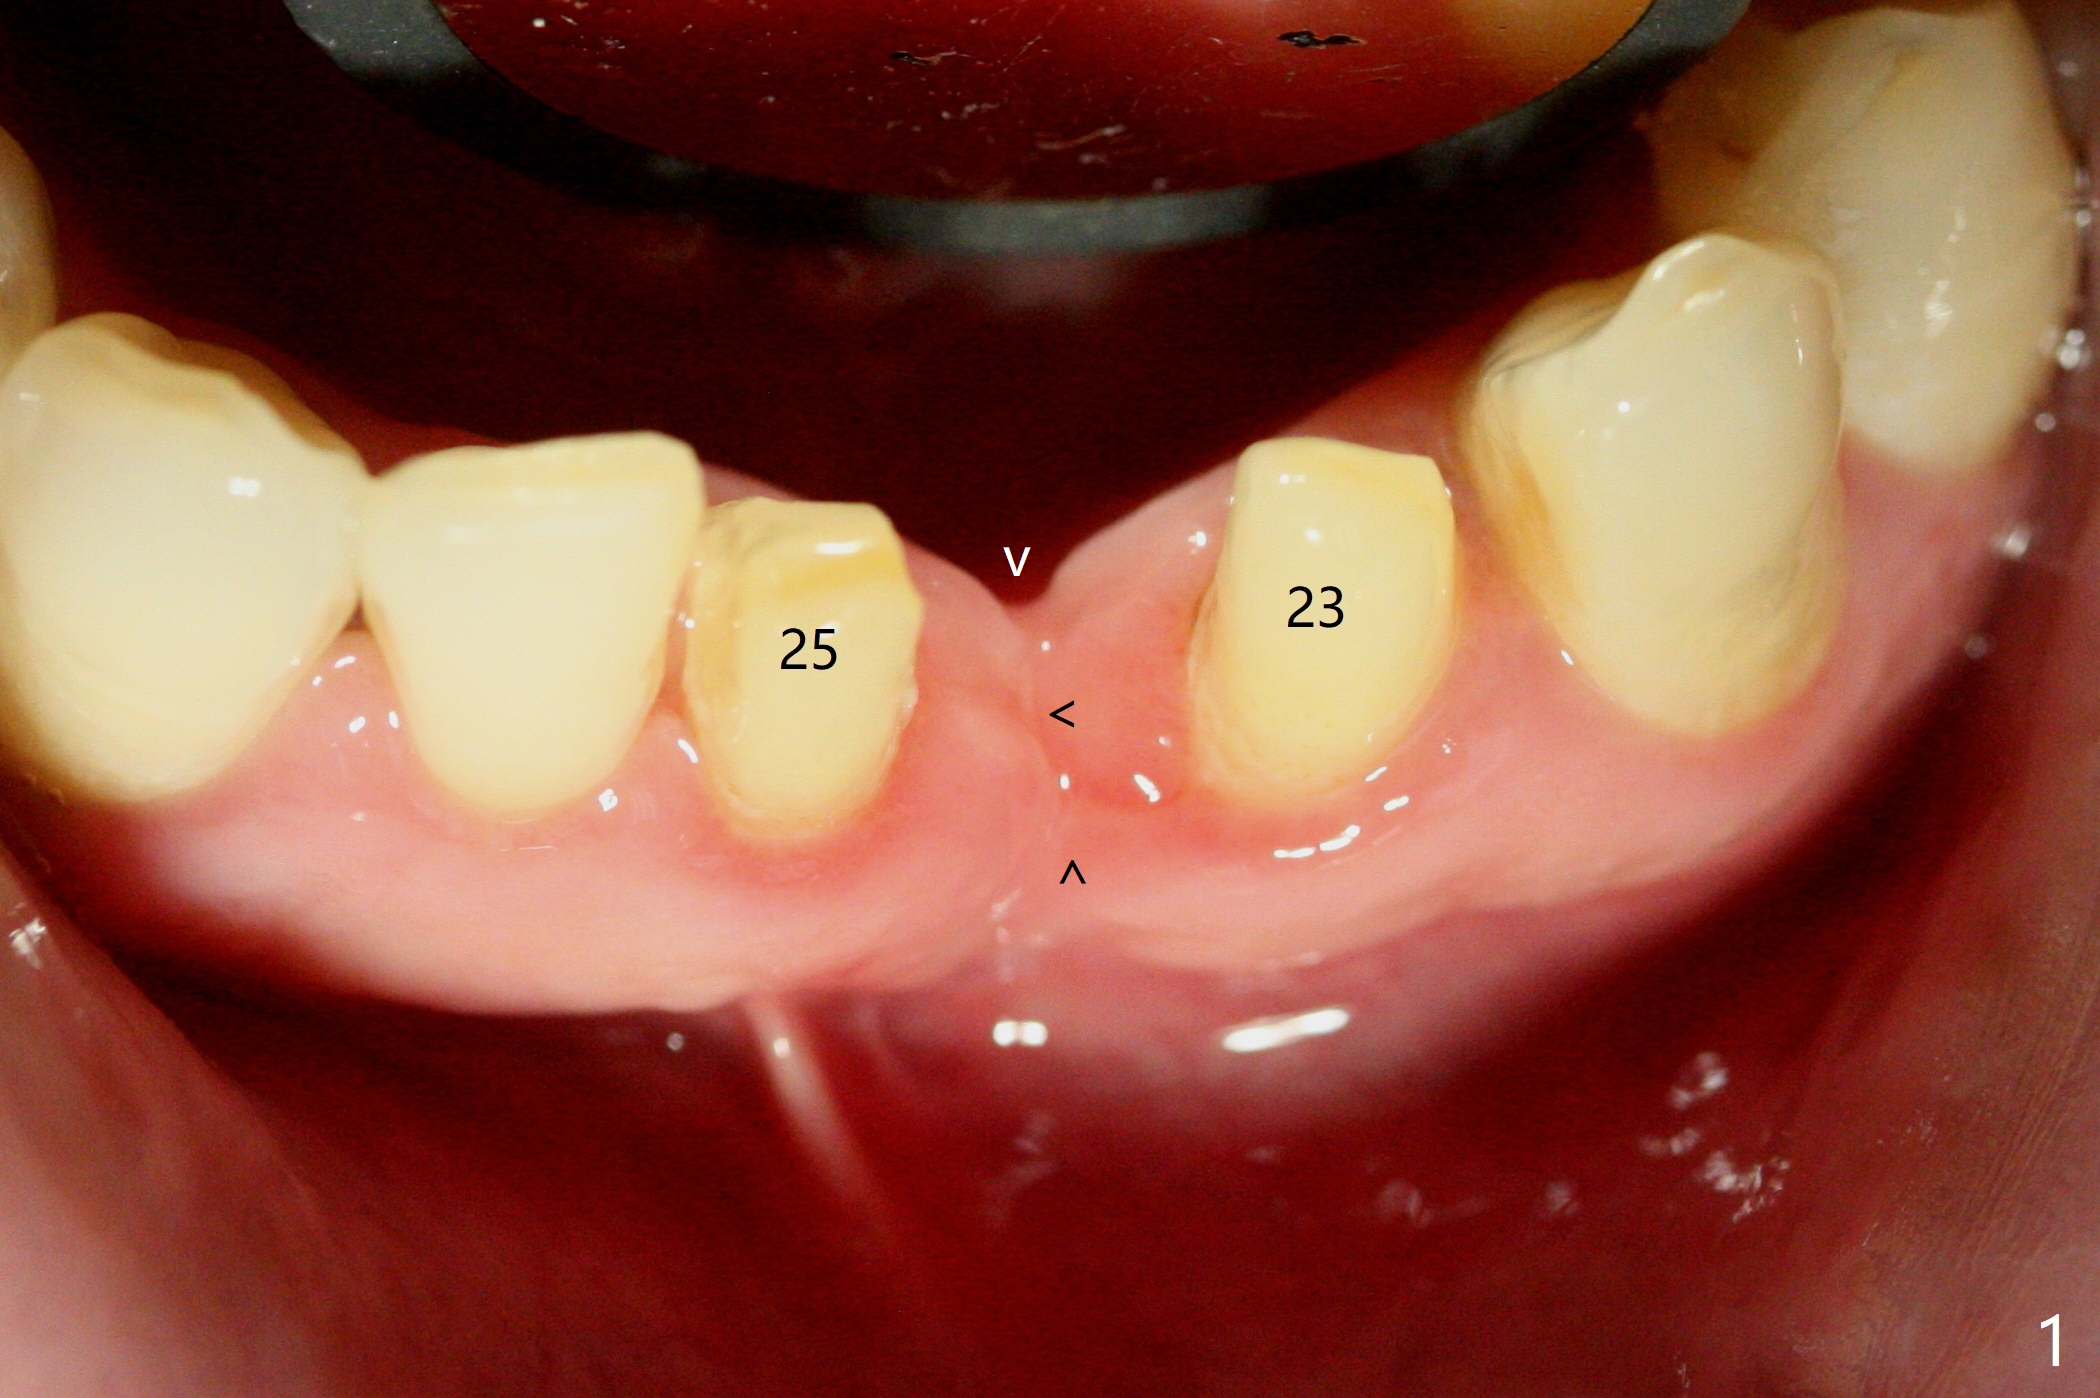

经过深洗以及改善口腔卫生,术前下前牙区牙龈基本没有红肿,但是缺牙处牙龈凹陷(图一,二:箭头),这个现象代表什么?如何影响手术进路?其实后者部分是因为牙龈与下面骨质(骨嵴)粘连(图三:*)产生的,分离粘骨膜瓣时不小心撕裂颊侧牙龈(图三(骨膜分离器下面:#),造成后来缝合困难,需要多用一个胎盘膜)。如果术前仔细分析CT 3D图像(图四,五)可以发现严重颊侧骨壁凹陷(图三:^)以及骨嵴(图四:*),事先抽血制备PRF膜和粘性骨粉,植骨效果好些(图六)。术中发现缺损,再抽血会拖延手术。最后将就用血调袢骨粉,使用胶原膜和胎盘膜覆盖(图七,八)。颊侧裂口术后十天愈合了(图九,十)。术后一个月颊侧牙龈凹陷,牙桥边缘(图十一:箭头)粗糙,临时牙桥取出,调整边缘,有利于局部卫生(图十二)。术后两个月桥边缘光滑(图十三:箭头),局部卫生和牙龈凹陷有所改善。病人将一个半月后回来取模。Return to Protect Graft 前磨牙即种 101 Xin Wei, DDS, PhD, MS 1st edition 04/30/2021, last revision 07/03/2021